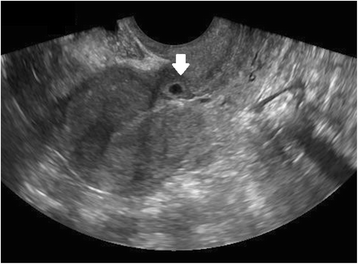

Ultrasound criteria for diagnosis of an interstitial ectopic pregnancy include a gestational sac at least 1 cm lateral to the edge of the uterine cavity, with a thin (5 mm or less) layer of overlying myometrium surrounding it (Figs. 3 and 4) [99, 100]. An ‘interstitial line’ may also be seen (Fig. 5) [101].

Interstitial ectopic pregnancy by transvaginal ultrasound. The arrow indicates thin (<5 mm) myometrium overlying the ectopic pregnancy. This finding by ultrasound, in combination with the lateral location of the gestation, has a reported specificity of 88-93 % but a sensitivity of just 40 % [101].